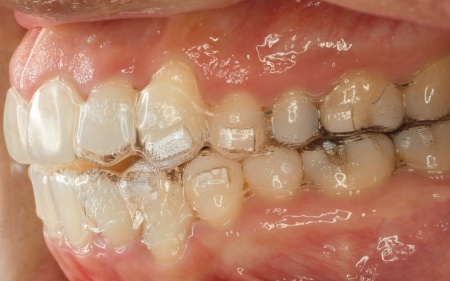

そのため、今回はマウスピース型矯正装置「インビザライン・コンプリヘンシブ」による矯正治療と、舌の癖を改善するトレーニング「MFT(口腔筋機能療法)」を併用することを提案し、同意いただきました。

今回は、奥歯を少し押し込みながら前歯が噛み合うように治療を行う方針です。

また、治療の際は上下の歯にかける「顎間ゴム」を併用しています。

これは上下の歯の位置関係を調整し、前歯の噛み合わせを整えるためのものです。

治療期間中は定期的に来院いただき、歯の動きや噛み合わせの調整を行いつつMFTも並行して実施し、正しい舌の使い方の訓練を行いました。

最後に、歯並びが整い前歯で噛めるようになったこと、舌の癖が改善されたことを確認し、治療を終了しています。